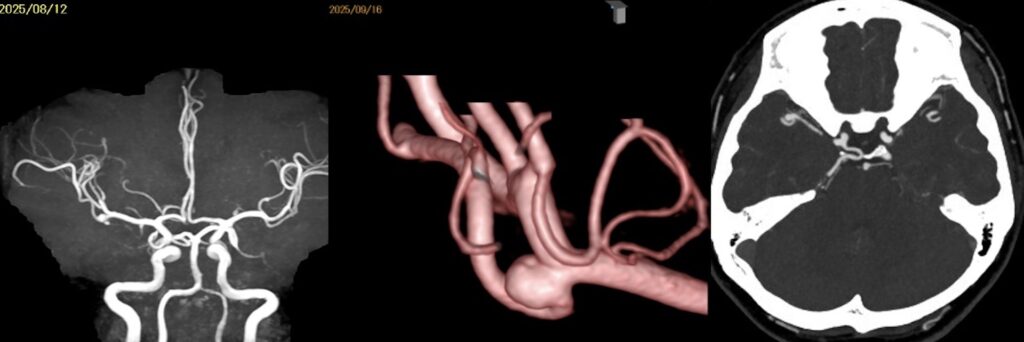

59歳女性の右中大脳動脈瘤を鍵穴クリッピングをしました。後遺症なしでした。 2025 12/12 脳動脈瘤・鍵穴 2025年12月12日13年前にくも膜下出血を起こしunknown SAHと診断され経過を見てきた患者さんに動脈瘤が徐々に育ってきたケースです。鍵穴クリップで対処しました。ScreenshotScreenshotScreenshotScreenshotScreenshotScreenshotScreenshotScreenshot 脳動脈瘤・鍵穴 よかったらシェアしてね! URLをコピーしました! URLをコピーしました! 251024金 橋本信夫先生に久しぶりにお会いしました。 251029水 第84回日本脳神経外科総会(パシフィコ横浜)初日 この記事を書いた人 kikuta 関連記事 未破裂中大脳動脈瘤の鍵穴クリッピング術を行いました。後遺症を認めませんでした。 2026年4月27日 2026年2月 52歳女性 左内頸動脈-眼動脈分岐部動脈瘤クリッピング術を行いました。 2026年3月21日 56歳女性 内頸動脈眼動脈分岐部動脈瘤クリッピング術をしました。軽度視野欠損が出ましたが無事退院されました。 2026年2月19日 63歳男性、右内頸動脈瘤開頭クリッピング術 2026年1月6日 58歳男性 中大脳動脈瘤を鍵穴クリップしました。合併症なく退院されました。 2025年12月17日 44歳女性 SAH PICA遠位部動脈瘤クリッピングを指導しました。 2025年12月17日 2025年5月 68歳女性未破裂Acom 動脈瘤6.6mmのクリッピング術 2025年9月26日 前交通動脈瘤をクリッピングしました 2025年2月26日